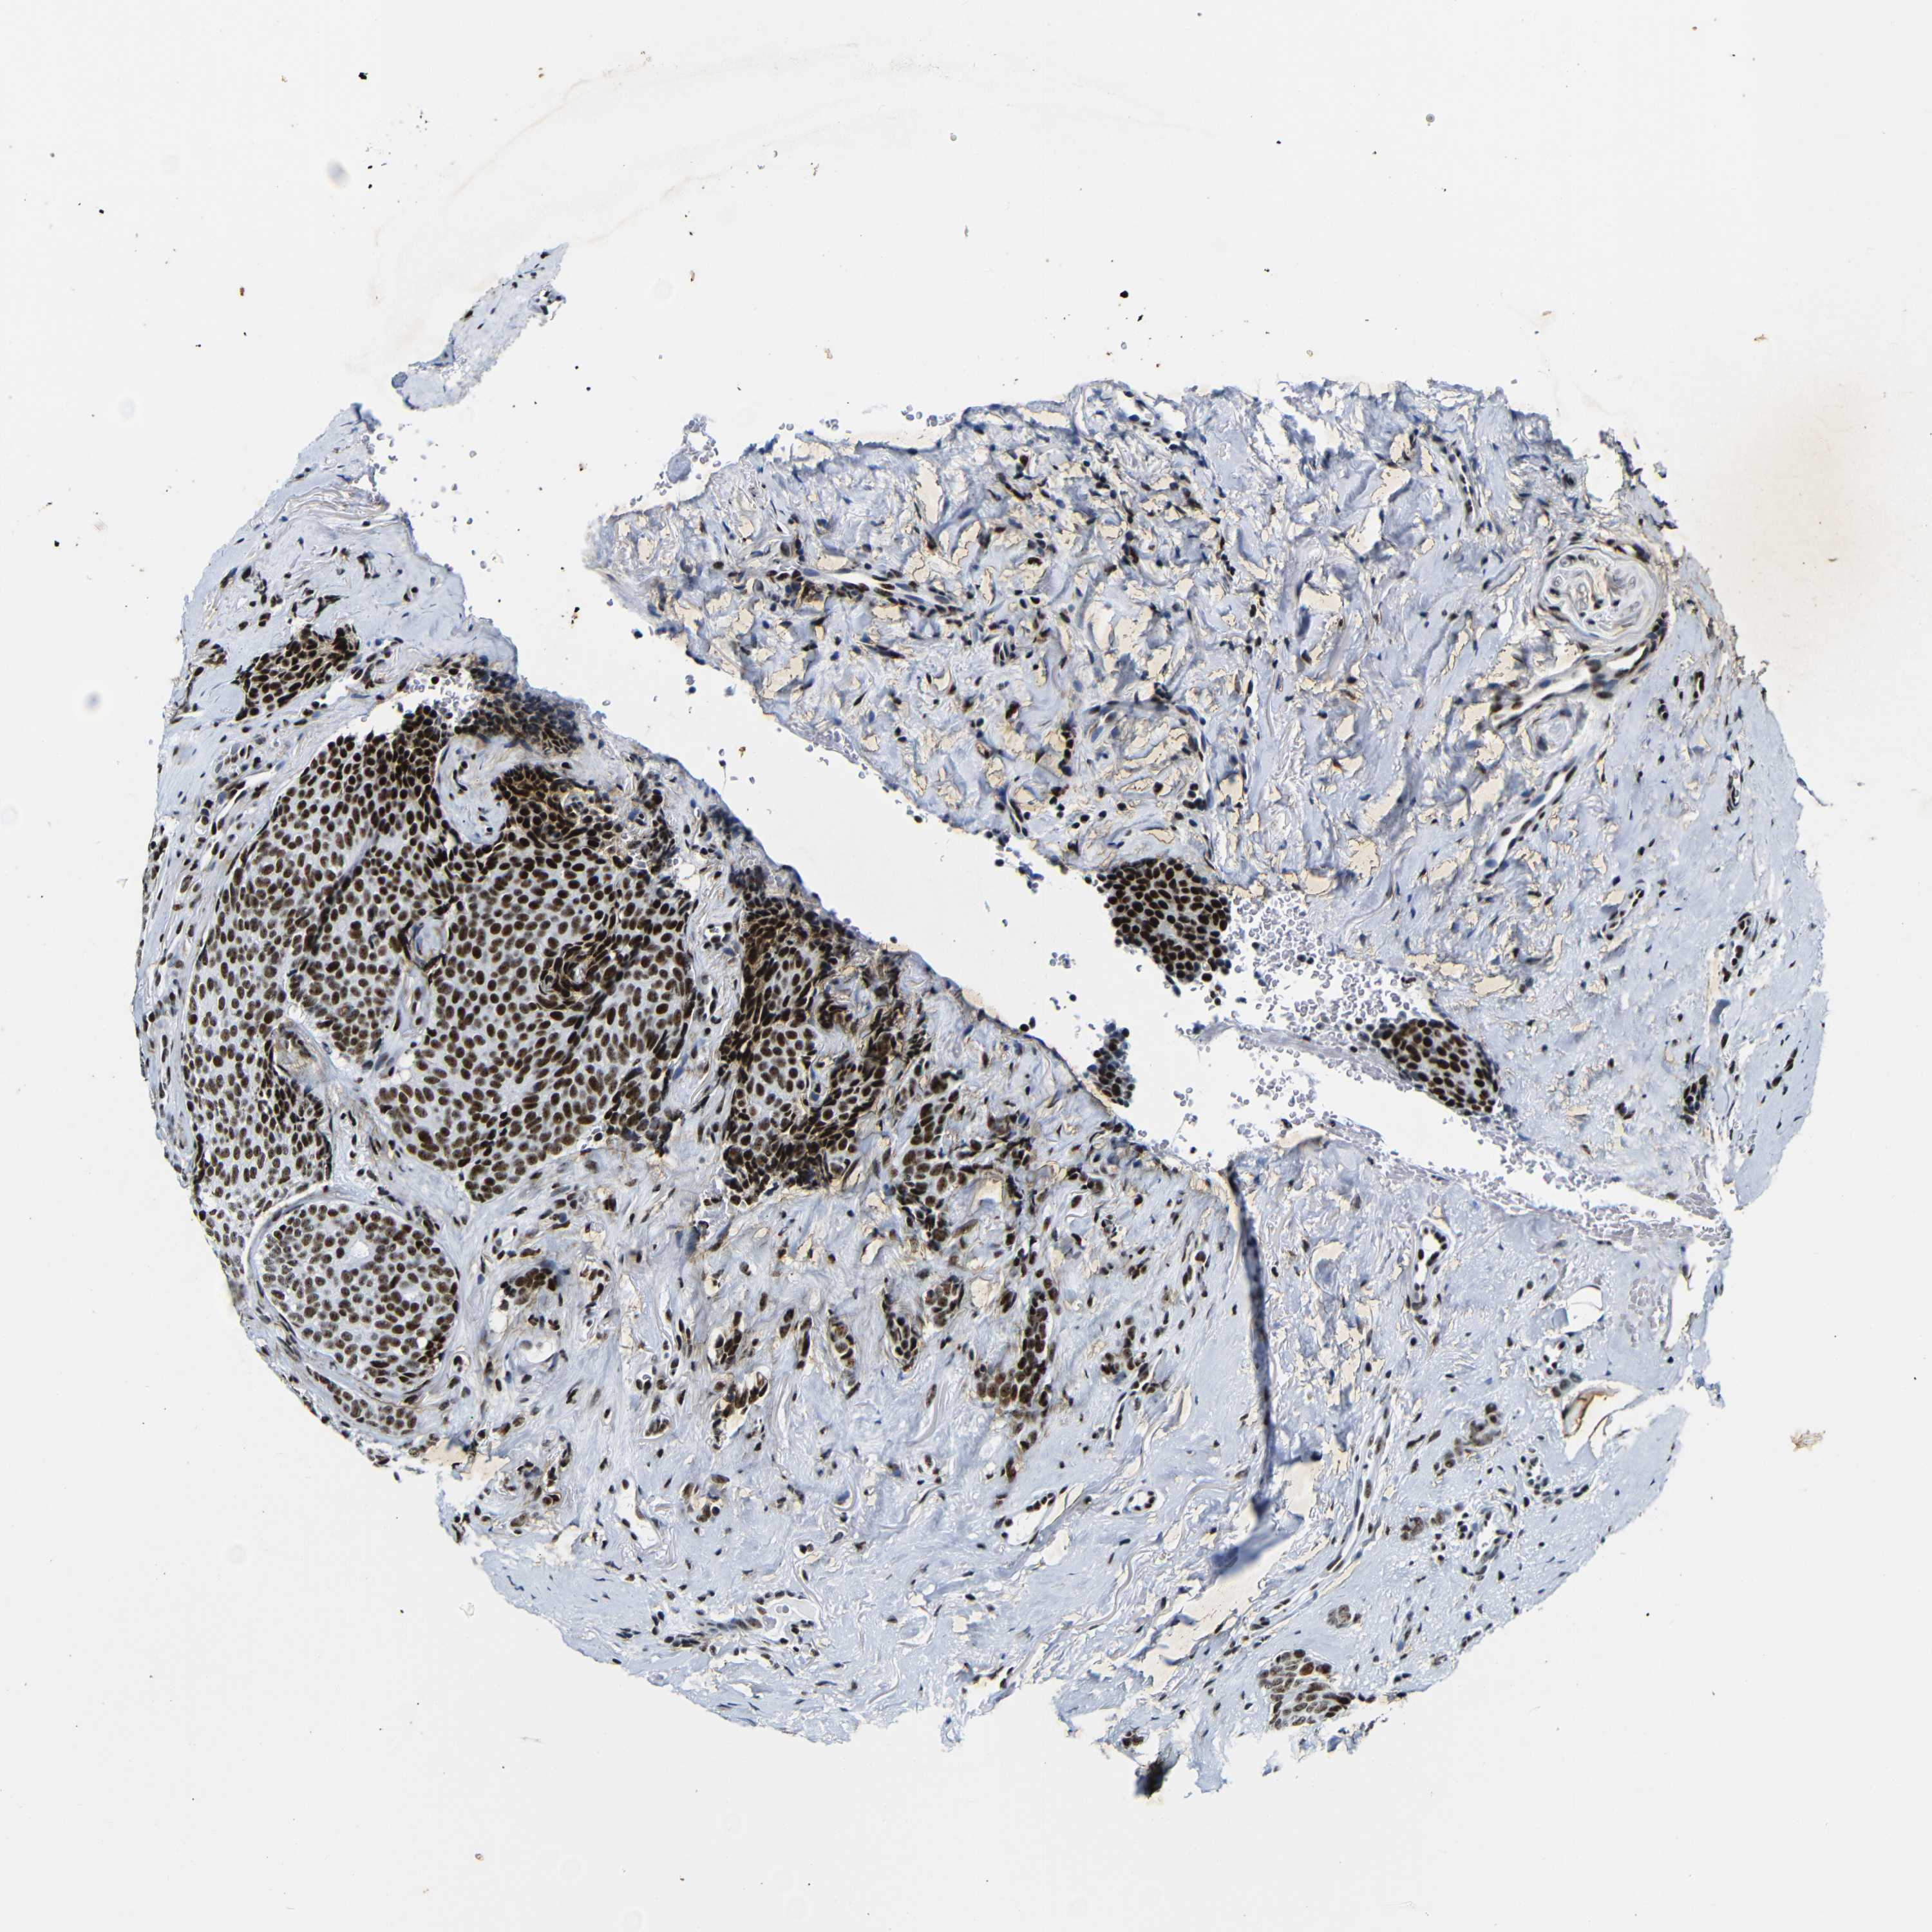

CANCER BREAST CANCER Show tissue menu

BRCA TCGA BRCA VALIDATION PROTEIN EXPRESSION